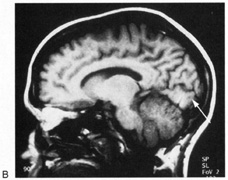

Fig. 10. Striate quadrantanopia. A. A 68-year-old woman with a stroke 3 years previously, causing left inferior quadrantanopia. B. MRI shows infarct of the superior bank of the right calcarine cortex.

Selective lesions can also occur along the anterior-posterior extent of striate cortex. A lesion of the occipital pole alone causes homonymous central hemiscotomata (Fig. 11).44,50 This can occur with watershed infarcts during systemic hypoperfusion. Slightly more anterior lesions in the middle zone of striate cortex cause homonymous peripheral scotomata (Fig. 12). The highly congruent, homonymous nature of these defects and their restriction to one hemifield differentiate these from ocular causes of central or paracentral visual loss. Lesions with such small field defects can be missed on CT.43 MRI with coronal sections through the occipital lobes should be performed, although even this may miss small lesions, particularly at the occipital pole.